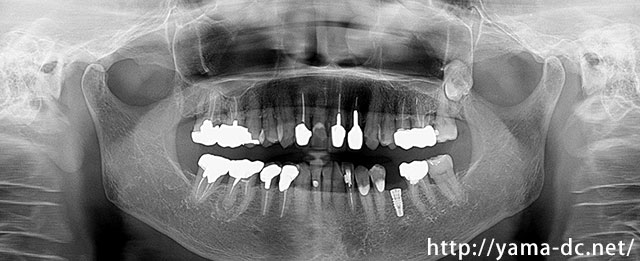

CTを用いることで従来の平面的なレントゲン画像では難しいとされる顎の骨を立体的に確認することができます。

きちんと神経の位置や骨の状態を確認した上で治療計画を立て、患者様に安心・安全なインプラント治療をご提供しています。

もっとも多い奥歯の1本欠損によるインプラント治療を説明します。